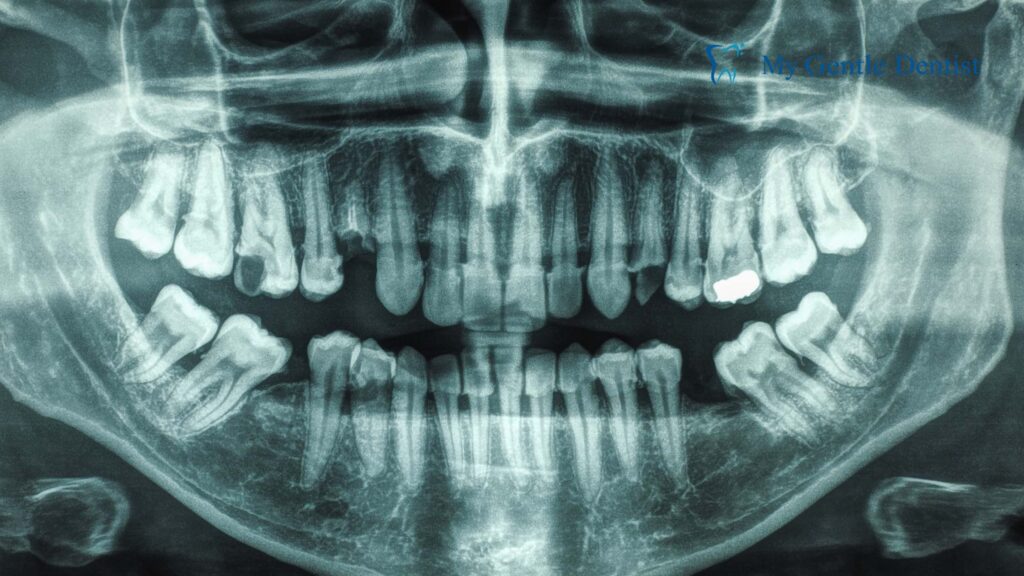

How Do Dental Implants Prevent Bone Loss in the Jaw?

At My Gentle Dentist, we understand how critical it is to choose the right solution for missing teeth. Beyond aesthetics and functionality, tooth replacement options should protect your overall oral health. Dental implants have become the gold standard, not only for their durability and natural appearance but also for their unique ability to prevent bone loss in the jaw. In this comprehensive guide, we’ll delve deeper into how dental implants help preserve your jawbone, their unmatched advantages, and why they’re worth considering for your smile restoration journey.

Dental implants are small titanium or zirconia posts that act as artificial tooth roots. They are surgically placed into the jawbone, where they fuse with the bone in a process called osseointegration. This fusion ensures stability and stimulates bone growth, effectively mimicking the natural function of tooth roots.